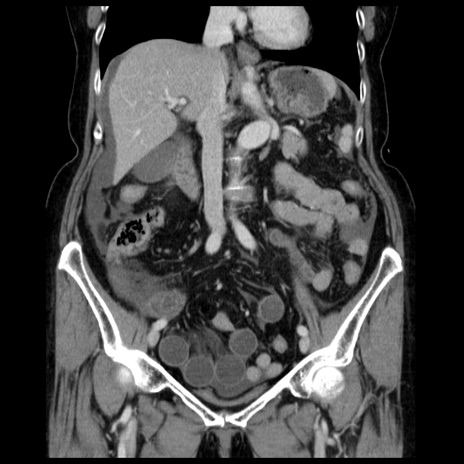

症例13(冠状断像)

【症例】70歳代女性

【主訴】腹痛、嘔吐

【現病歴】15時間程前(昨晩)より腹痛あり。今朝になっても症状の改善なく、嘔吐あり。腹痛も増悪あり、救急外来受診。

【既往歴】子宮癌全摘術後

【身体所見】意識清明、BP 121/72mmHg、P 74bpm、SpO2 100%(RA)、腹部:平坦・軟、腸雑音ほぼ聴取せず。下腹部・心窩部・臍左上に圧痛あり。反跳痛なし。

【データ】WBC 10600、CRP 0.15